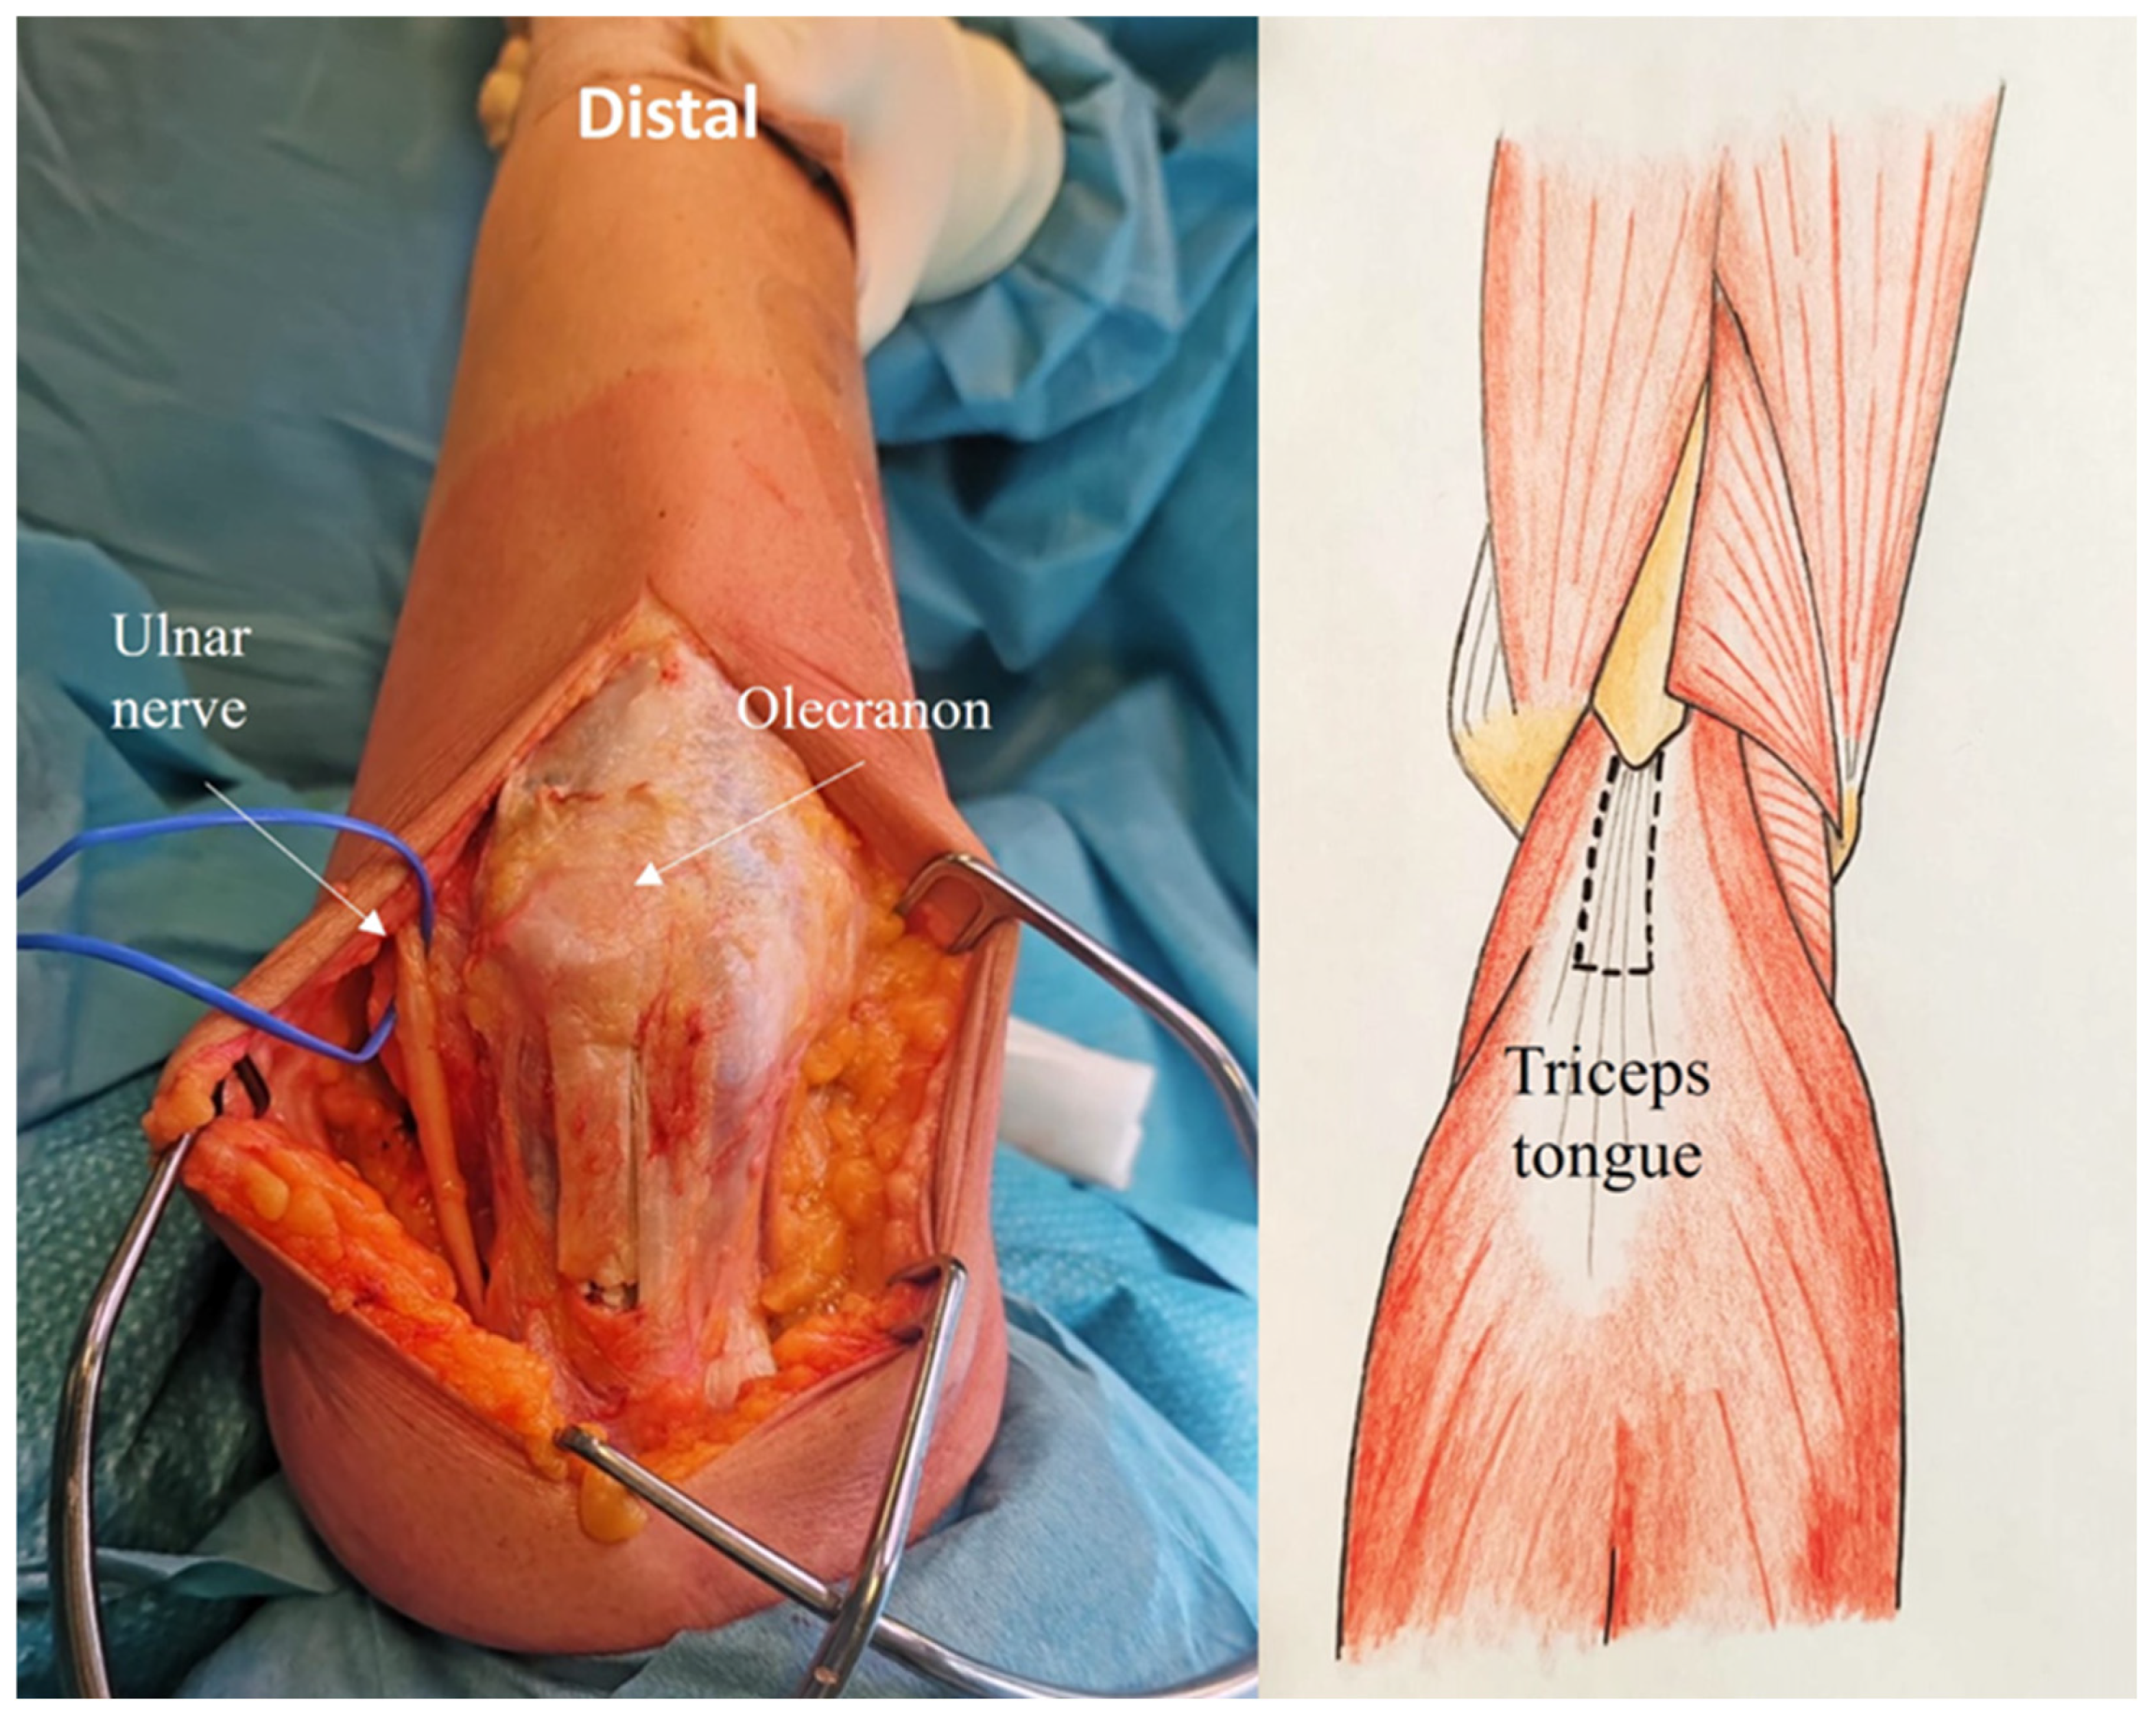

2.4. Development of the ARTT Approach